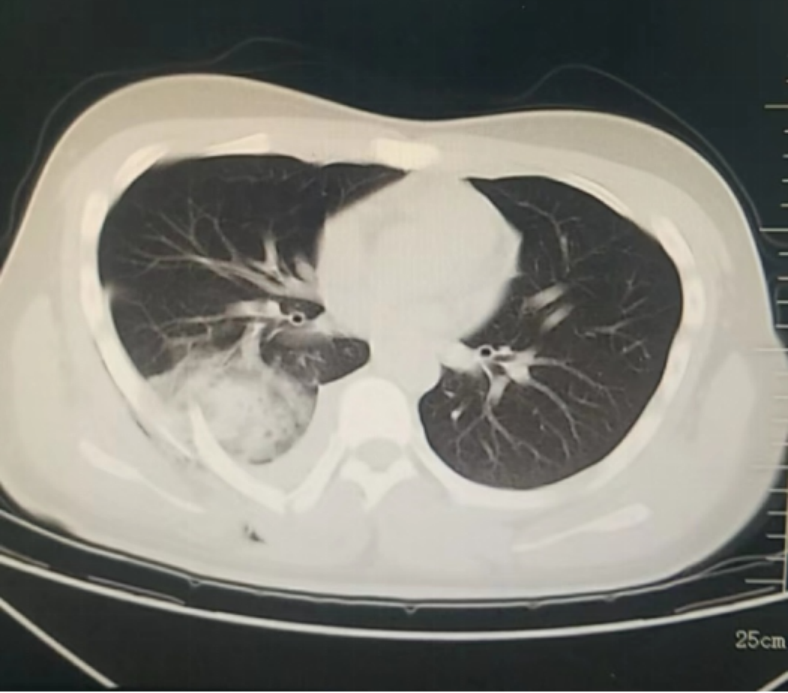

12月26日傍晚,哈医大四院松北院区胸外科医生办公室响起了急促的电话铃声,松北院区急诊科请求紧急会诊一位“特殊”的外伤患者。受伤的小伙子小杨(化名)是一名在校大学生,从小在广州长大,初次来到哈尔滨被冰雪游乐项目吸引,在玩雪圈快速下滑的过程中,不慎背部受到重击,疼痛难忍。医生在电脑上调出电子胶片,不禁心头一惊,患者由于外伤导致右背侧肋骨骨折,恰好有一根断裂的肋骨像“匕首”一样刺入了右肺下叶,出现了严重的血气胸,如果不马上手术,随时可能出现失血性休克,情况十分危急。医院为患者开通绿色通道,救治工作有条不紊地进行。手术非常顺利,仅60分钟左右。在医护人员的护送下,小杨安全地回到了胸外科病房。第二天,小杨已经能够坐起来了,小杨父母紧紧握住医生的手,感激之情难以言表。